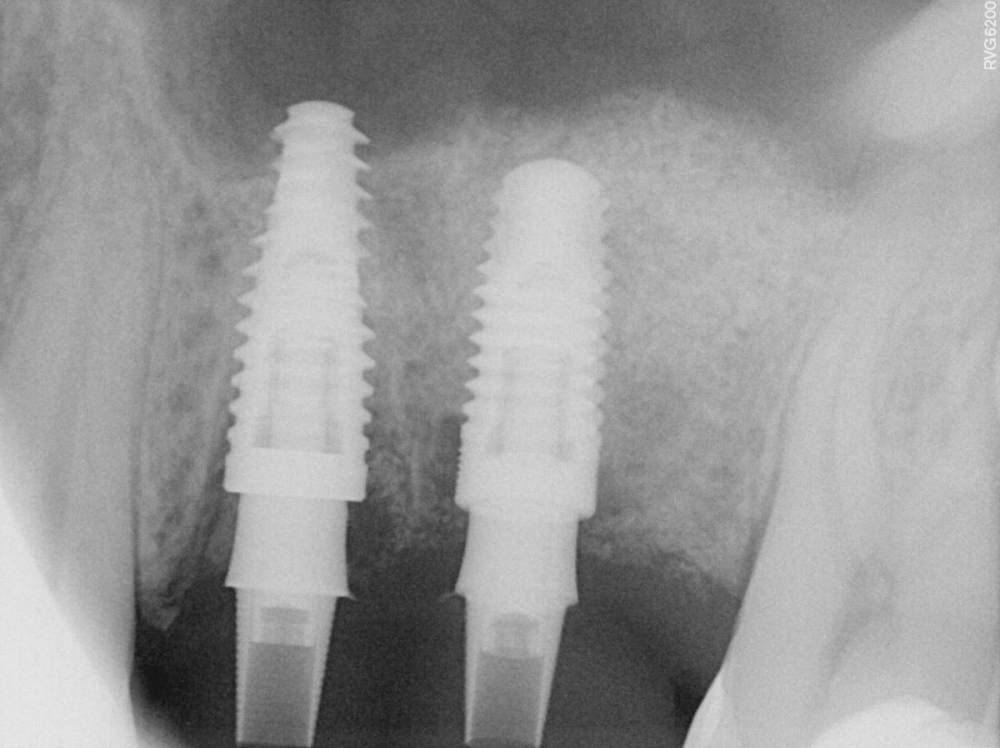

TIGER Опубликовано 8 мая, 2023 Автор Поделиться Опубликовано 8 мая, 2023 Всем привет!планировал удаление,но во время синуса решил использовать фрагмент как клин для стабилизации болта,в итоге совершил ошибку с более медиальной позицией 26,ибо шаблон не изготовил....через 5 мес одел времяхи,т.к будет тотал Ссылка на комментарий